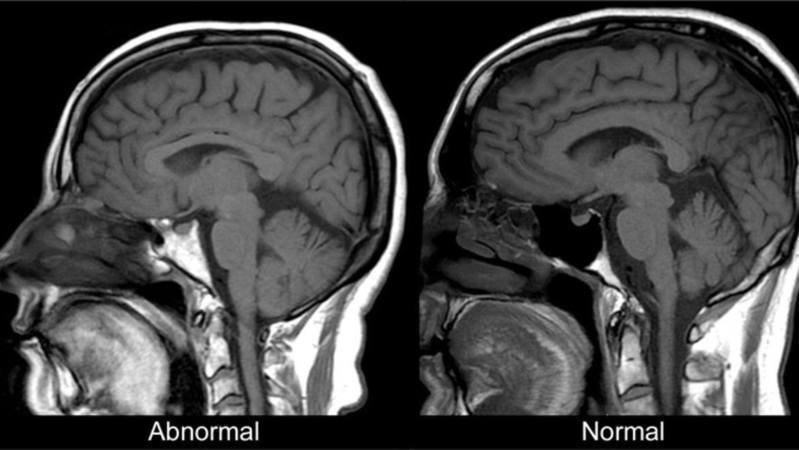

It has been a while that people want to get more attention about ALS disease with dousing bucketful of freezing water over their heads. This is to be discussed to what extend it helps but it is clear that we need to do more and more! To support this campaign is very important to get the attention of the health organizations and medicine producers with big budgets for the R&D facilities. Please support this campaign! We are starting with one of the biggest health company and will continue with many!